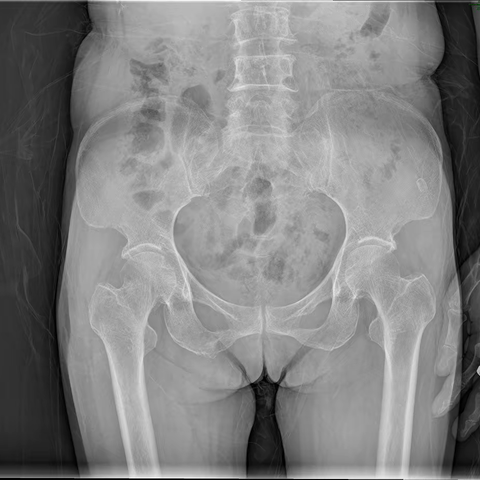

步入退休年龄的阿姨,10年髋部疼痛竟然是骨骼发育问题!?

2023-06-22 1130阅读

62岁阿姨,体型肥胖,关节不堪重负疼痛6年多,典型的前内侧膝关节骨性关节炎

2023-06-15 1275阅读